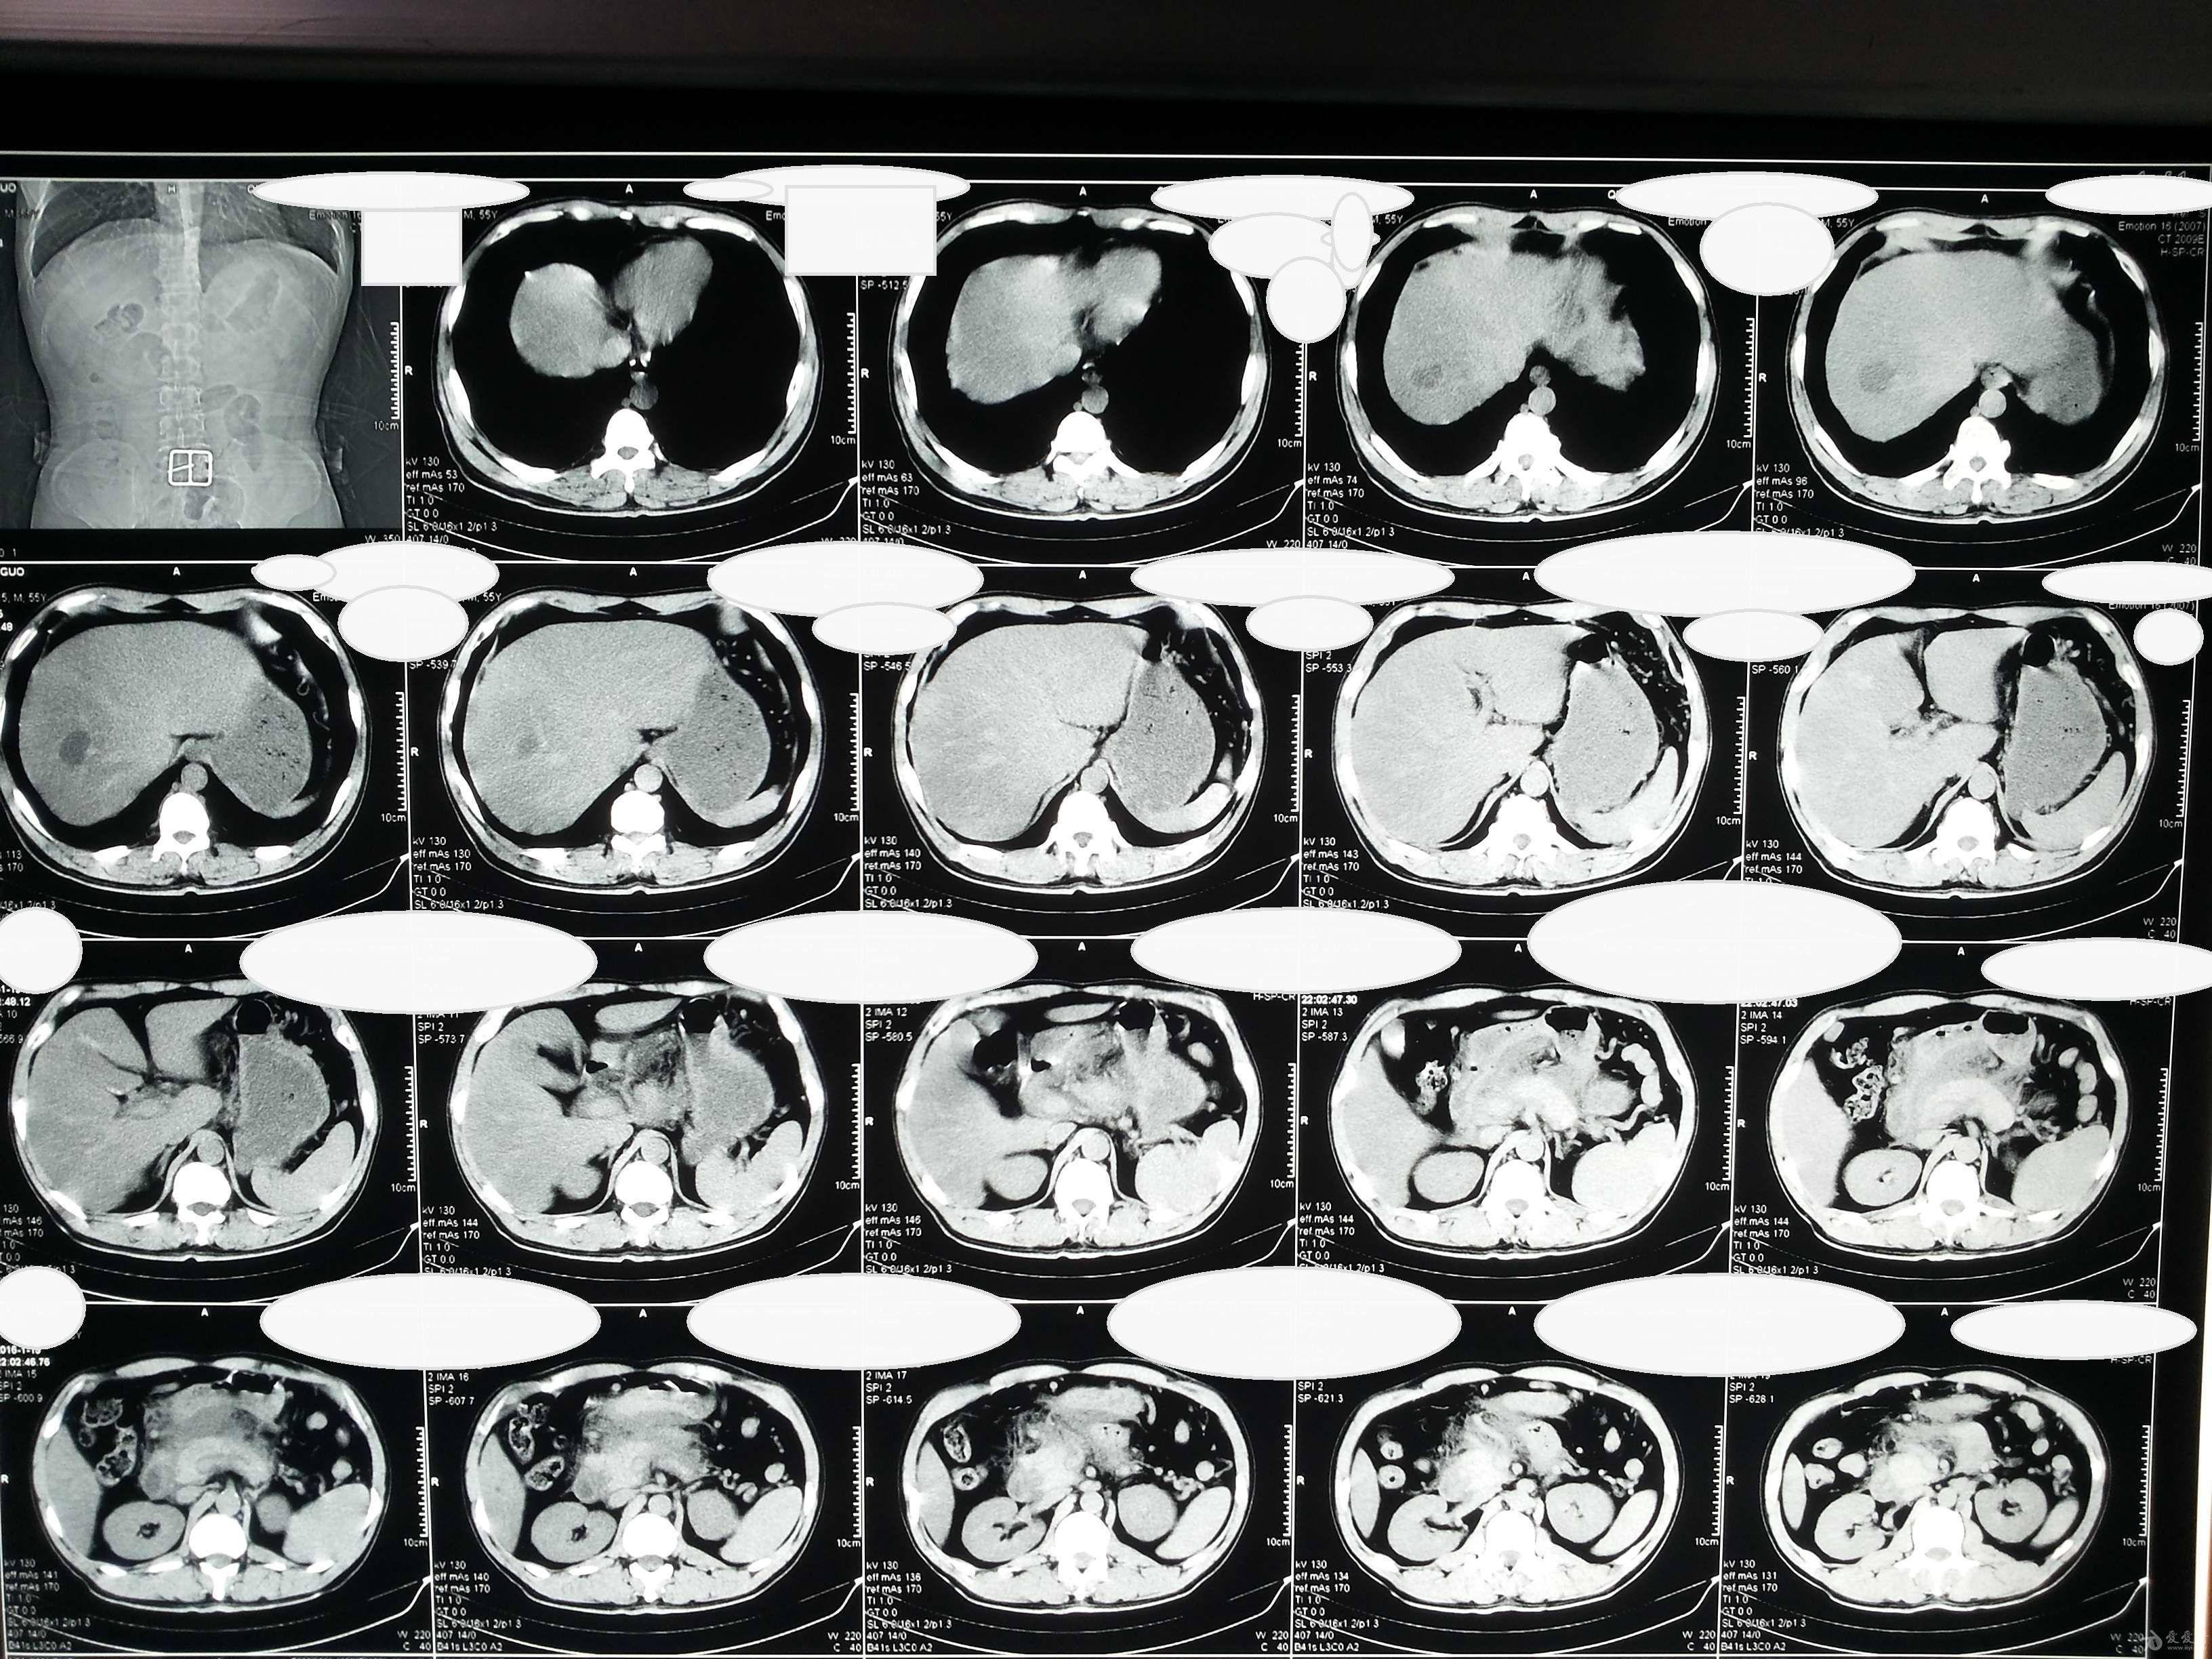

[读片]腹部/ct平扫 增强/病理已公布/20100316

请教大家腹部高密度影考虑什么,健康体检人员无任何临床症状